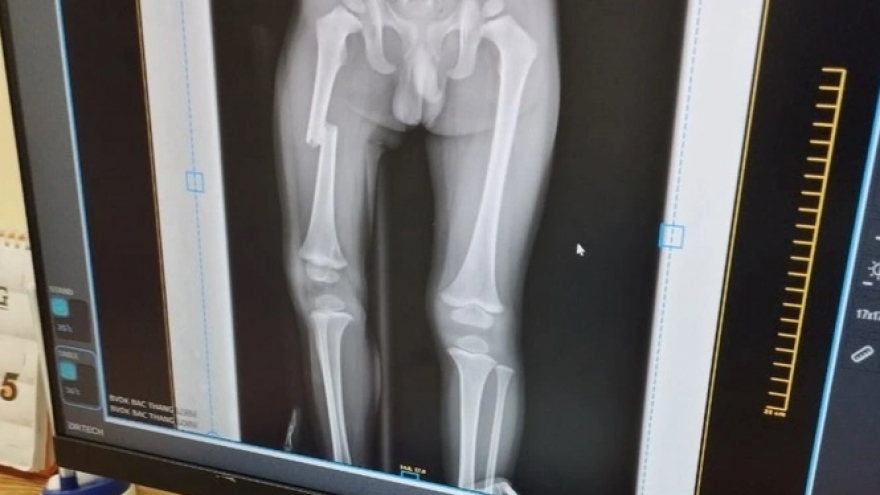

VOV.VN - Thay vì phải phẫu thuật để tiến hành nẹp vít, hiện nay nhiều trường hợp gãy xương ở trẻ em đã được can thiệp điều trị tối thiểu tại Bệnh viện đa khoa Xanh Pôn. Bệnh nhi ít đau đớn và nhanh phục hồi vận động.